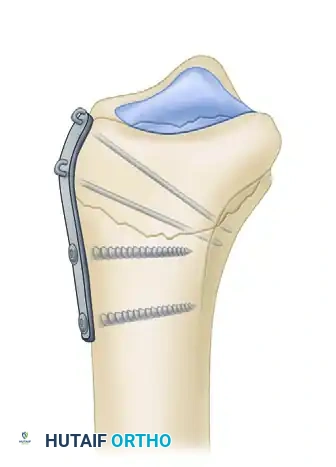

FRAGMENT-SPECIFIC OPEN REDUCTION AND INTERNAL FIXATION

Recognizing the biomechanical pitfalls of isolated Kirschner wire fixation and standard plate-and-screw constructs—especially when dealing with highly comminuted intra-articular fractures in osteopenic bone—Medoff developed a comprehensive wrist fixation system. This system (commercialized as the TriMed system) combines the principles of pinning and plating to achieve stable, fragment-specific reconstruction of the distal radius.

Thin metaphyseal cortical bone does not hold standard screws well. Furthermore, conventional thick plates cannot be applied easily to the dorsal aspect of the distal radius due to the high risk of extensor tendon irritation and eventual rupture. Fragment-specific fixation utilizes low-profile wire-forms and pin-plates to capture these specific fragments without adding excessive bulk.

Biomechanics of Pin-Plate Fixation

Traditional radial styloid Kirschner wire fixation provides only a single point of constraint. This single point of fixation acts as a pivot, failing to prevent settling, bending, or radial drift of the distal fragments under physiological loads.

By adding a small buttress plate to the radial styloid pin, the construct is transformed. The pin-plate provides two distinct fixation points: the first through the distal end of the plate, and the second through the intact medial radial cortex. This dual-point constraint prevents collapse, resists dorsal torque, and halts radial migration.

Fragment-Specific Implants and Application

1. The Radial Pin-Plate:

Applied to the radial column, this implant enhances stability by providing a radial buttress. It effectively neutralizes bending forces that would otherwise cause the radial styloid to displace proximally and radially.

2. The Ulnar Pin-Plate:

The dorsal ulnar fragment (often involving the sigmoid notch) is stabilized with an ulnar pin-plate. By proper contouring, this plate can close gaps in the sagittal plane,